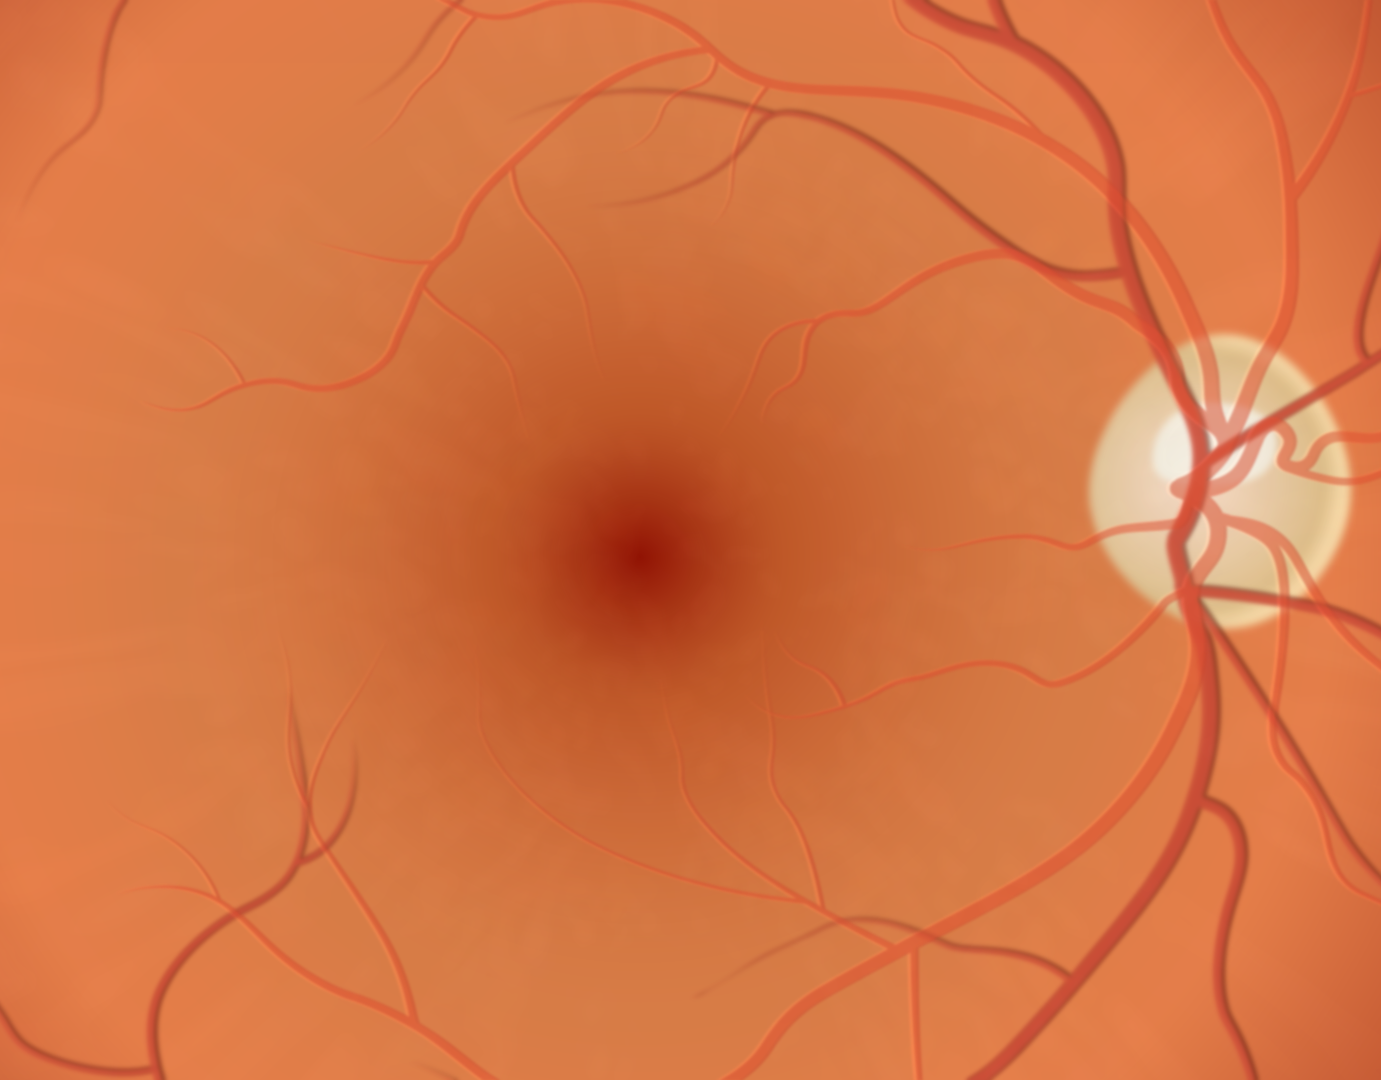

Ophthalmology

Illustrating eye diseases and conditions